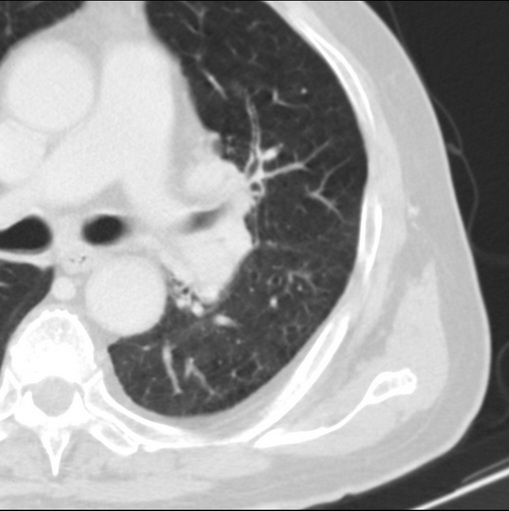

男性患者 81岁 咳嗽 咳痰 咯血

支持左侧中央型肺癌伴肺门及纵膈淋巴结转移。

肿块贴近左肺门,包绕左上肺动脉,形态不规则。肿块增强扫描中度强化。纵膈内主动脉弓左旁间隙、气管隆突前、下间隙见多枚淋巴结影。综上考虑左侧中央型肺癌可能性大。图片没有完整上传,尤其是左肺上叶支气管分支层面没有上传,因此不好判断是叶支气管中断还是段支气管中断。另外,下图红色部分所示是“黏液支气管征”吗?